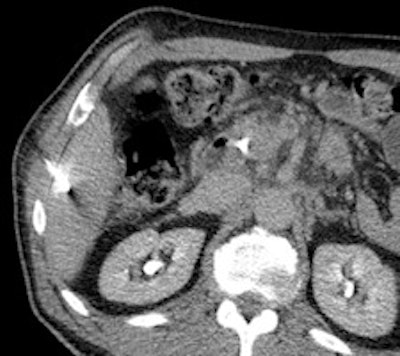

A 50-year-old man with history of pancreatic carcinoma underwent a CT-guided biopsy (above), which was nonconclusive (pathology result: normal liver tissue). Three weeks later, an MR-guided biopsy (below) was performed, and the biopsy revealed a cavernous hemangioma. Images courtesy of Dr. Rüdiger Hoffmann.